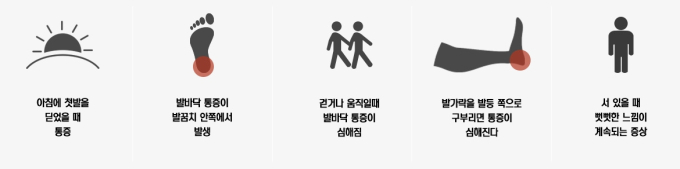

그런데 문제가 생겼다. 어느날 아침부터 발바닥에 찌릿한 통증이 생기기 시작했다. '운동을 너무 무리해서 했나' 생각하고 방치한 뒤 며칠이 지나자 A씨는 아침에 발을 내딛지 못할 정도의 통증을 느끼기 시작했다. 뭔가 심상치 않음을 짐작하고 수소문 끝에 발질환 전문 정형외과를 찾았다. 그 결과 A씨의 발 문제는 족저근막염 때문인 것으로 밝혀졌다.

족저근막은 우리의 걸음걸이와 관련이 깊다. 발꿈치뼈(종골)와 발가락뼈를 이어주는 부채꼴 모양의 막을 족저근막이라고 부르는데 이 막이 우리 발바닥에 아치를 만들면서 충격을 흡수한다. 일종의 '쿠션' 역할을 하는 부위다. 그러나 우리의 체중을 지지하고 있는 만큼 위험에 쉽게 노출된다. 오래 서있거나 자주 걷거나 달리는 것을 주 업무로 하는 경우 족저근막에 계속적인 압력이 가해지면 미세한 상처가 된다. 이 상처는 족저근막염으로 발전하는 경우가 많다.

이미 족저근막염이 생겼을 때 역시 적극적인 치료가 필요하다. 초기에는 80% 이상 약물 및 물치치료러 개선이 가능하지만, 통증을 그대로 놔둔 채 방치하게 되면 수술이 불가피해질 수 있다. 말하자면 호미로 막을 것도 가래로 막아야 하는 사태가 올 수 있다는 뜻이다. 발에 문제가 생기면 방치하지 말고 곧바로 정형외과를 방문, 정확한 원인을 규명하고 적절한 대책을 강수하는 것이 중요하다.